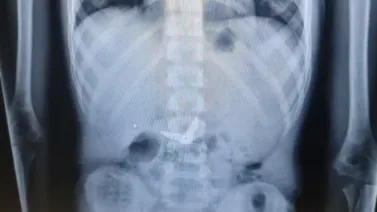

לאחר צילום הרנגטן בו נראו המספריים כאשר הלהבים נמצאים במצב פתוח בקיבה, הוזעקו צוותים רפואיים בתחומי כירורגיית וגסטרו ילדים, לרבות מומחה לפרוצדורות אנדוסקופיות בילדים בשערי צדק, ד"ר אורן לדר, והוחלט להכניס את י' לחדר הניתוח באופן דחוף כדי להוציא את המספרים.